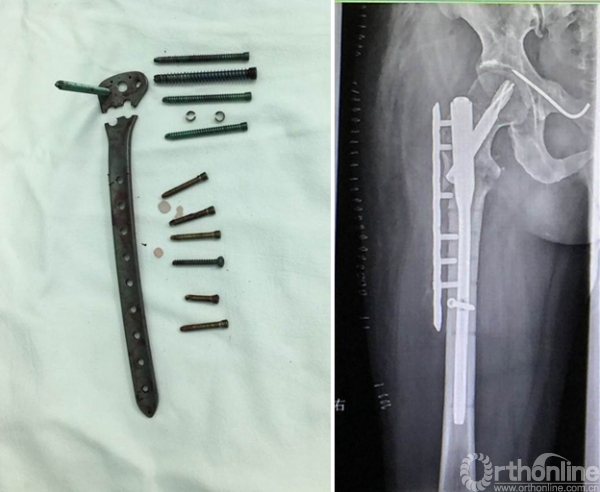

1.进针点错误导致髋内翻和固定失败;

2.辅助捆绑带或阻挡钉能增加骨折稳定性促进愈合;

3.骨折近端头颈的不稳导致髓内钉固定的失败;

4.正确的进针点和足够的髓内钉长度,即使不能达到解剖复位,也能收到满意的愈合结果;

5.内侧粉碎和钢板远端螺钉数量不足是失败原因之一;

6.长阶段劈裂骨折非解剖复位反而增加骨痂量收到满意效果。